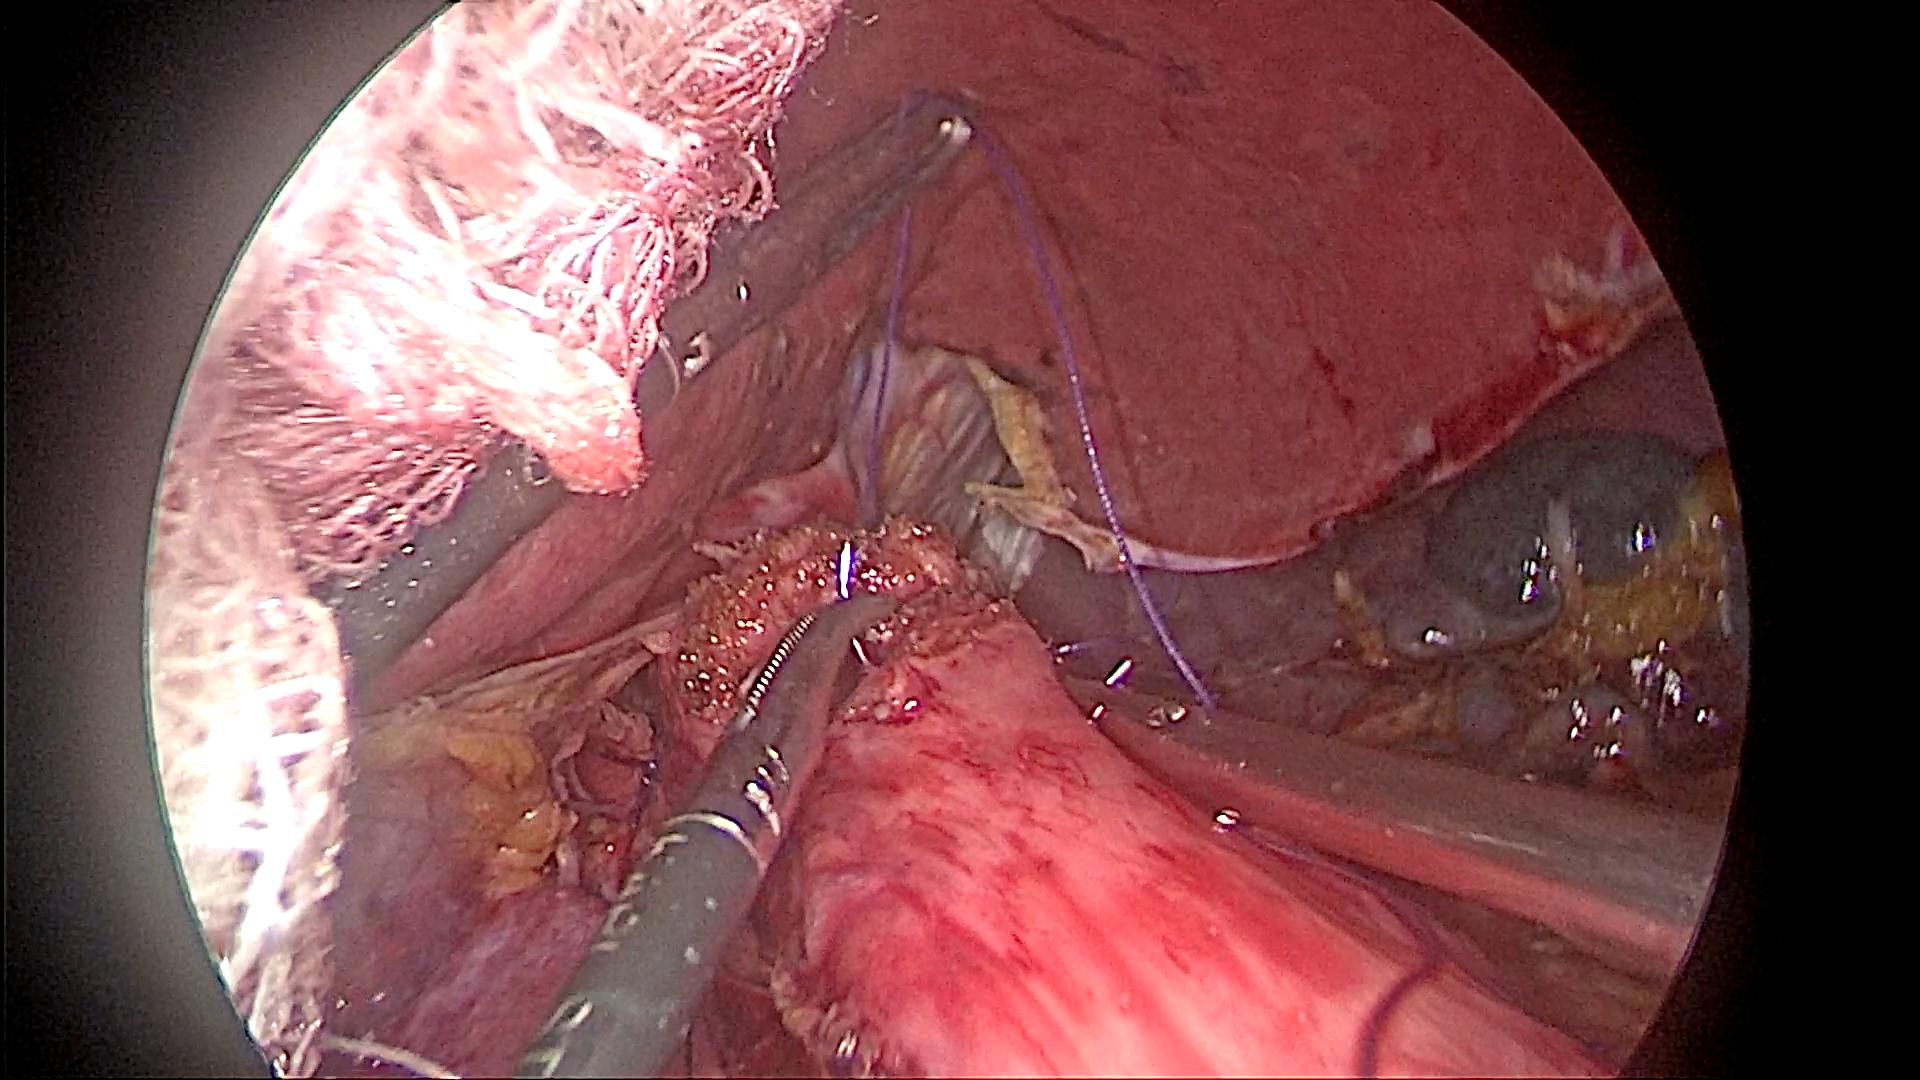

91 tuổi, phát hiện bị ung thư dạ dày và sức khỏe lại không được tốt, các con của bà Hoàng Thị K dự định chọn giải pháp chăm sóc giảm nhẹ để bà bình an đi nốt con đường chứ không muốn phẫu thuật vì sợ bà phải chịu thêm đau đớn. Tuy nhiên, khi xin ý kiến mẹ mình, thì bà K lại bảo: Mẹ xem tivi, nghe đài, đọc báo nhiều nên biết Bệnh viện Bạch Mai đang áp dụng nhiều kĩ thuật tiên tiến trong phẫu thuật và đã cứu sống được rất nhiều người mắc bệnh hiểm nghèo. Thể theo nguyện vọng của mẹ, ông Ngô Thanh S (con trai bệnh nhân) đã đưa mẹ đến khám tại Trung tâm Tiêu hóa – Gan mật, Bệnh viện Bạch Mai. Sau khi nội soi, chụp chiếu và làm các xét nghiệm cận lâm sàng cần thiết, bà được chuyển sang Khoa Phẫu thuật Tiêu hóa – Gan mật tụy. Tại đây, các bác sĩ nhận định bệnh nhân K có chỉ định phẫu thuật nội soi cắt đoạn dạ dày, nạo vét hạch. Với sự giúp sức của Trung tâm Gây mê và Hồi sức ngoại khoa, qua 5 lỗ nhỏ trên thành bụng, kích thước từ 0,5 đến 1 cm, các phẫu thuật viên của Khoa phẫu thuật Tiêu hóa – Gan mật tụy đã đưa camera và các dụng cụ nội soi tiếp cận, phẫu tích, bóc tách dạ dày và các mạch máu, hạch liên quan.

Phẫu thuật nội soi hoàn toàn cắt đoạn dạ dày, miệng nối dạ dày – ruột sử dụng dụng cụ ghim cắt thẳng kết hợp khâu tay đóng lỗ đặt máy (BN Trần thị N)